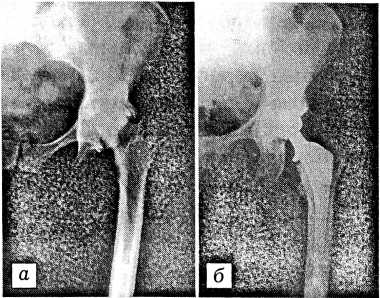

Рис. 3. Рентгенограммы больной Р. с двусторонним диспластическим коксартрозом.

а — состояние после первичного эндопротезирования левого тазобедренного сустава протезом Вирабова: протез нестабилен; б — после ревизионного эндопротезирования цементным протезом «Biomet».

В 62 случаях ревизионное эндопротезирование по поводу нестабильности протеза произведено больным, первично оперированным в других клиниках. Заменено 37 эндопротезов Сиваша, 4 протеза «Феникс», 2 — Мовшовича, 2 — Вирабова (рис. 3), 4 протеза Мура— ЦИТО и др.